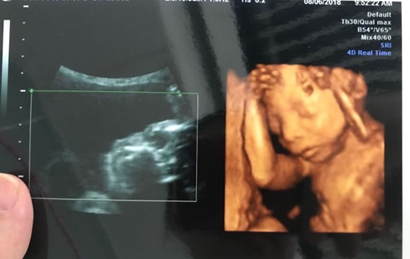

四维彩超是目前比较流行的孕检之一,四维能对胎儿头面部立体成像,可清晰显示胎儿的状态,网上很多四维是女孩但是却生了男孩的案例,那么四维女孩翻盘几率大吗?

四维一般都是二十四周以后照的,这么大的孕周出错的机会还是比较小的,虽然不是百分之百准确的,但是出错的概率还是会比较少的,大部分情况都是不会出现翻盘的情况,四维超声同其它超声检查相比,可以实时观察人体内部器官的动态运动,也能准确地分辨出胎儿的性别。虽然四维彩超能够看清胎儿的性别,但在检查过程中,为了避免透露胎儿的性别,医生会主动的回避胎儿的性别特征以及下半身,因此最好找熟人的医生做这样才能更准确知道宝宝的性别。